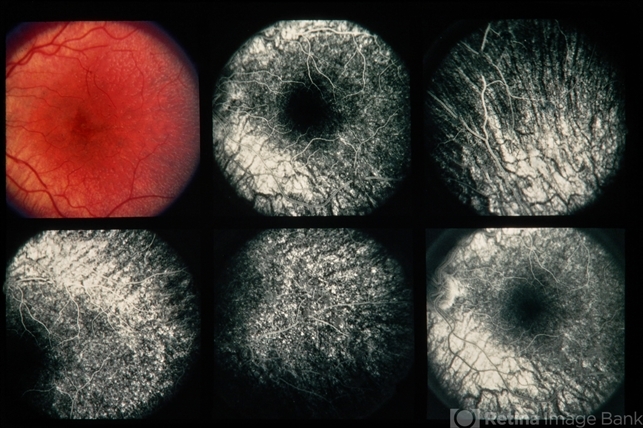

- 22-year-old white female. Fundus albipunctatus. 20/25- and 20/200.